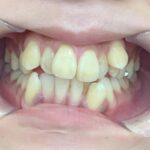

Before Braces - 治療前 -

犬歯と第一大臼歯のⅡ級関係が見られます。

また、前歯に過度なジェットが見られます。